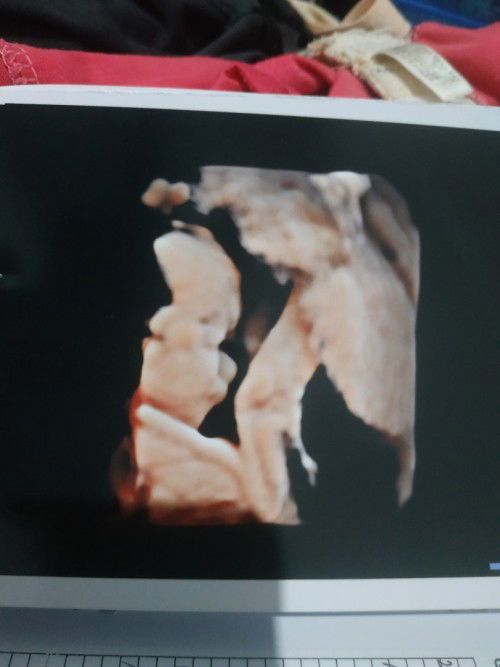

Usg 4d uk 18w

Usg 4d uk 18w jk katanya cewek, ada kemungkinan gk ya dokternya salah liat?😁